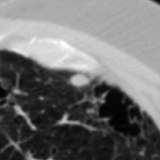

The current study focuses on lung nodule retrieval from a database of CT scans, where patches taken from CT slices of pulmonary nodules are to be mapped into an embedding. LIDC-IDRI [5] is a dataset of thoracic CT scans of 1,010 patients. All the scans were annotated by up to four radiologists, where each one identified, segmented and evaluated separately the lung nodules of a diameter above . Their evaluation also included ratings for a set of 9 characteristics: Subtlety, Internal structure, Calcification, Sphericity, Margin, Lobulation, Spiculation, Texture and Malignancy. The rating system was based on a discrete score of 1-5. Four examples of nodule patches are illustrated in Figure 2: 2 benign (a, b) and 2 malignant (c, d). A rounded vector of the mean rating is bellow each nodule, with the characteristics ordered according to the listing above. The most prominent difference between a and b is the calcification: 3 (solid) and 6 (absent) accordingly. d compared to c has a more defined margin, is more lobulated, but less spiculated. The malignancy score is used to define malignancy classes: score of 1-2 is benign, score of 3 is unknown, and a score of 4-5 is malignant.

(a) Benign

3, 1, 3, 3, 4, 3, 1, 5, 1

(b) Benign

3, 1, 6, 5, 5, 1, 1, 5, 2

(c) Malignant

5, 1, 6, 3, 3, 4, 1, 5, 5

(d) Malignant

4, 1, 6, 3, 4, 2, 2, 5, 4